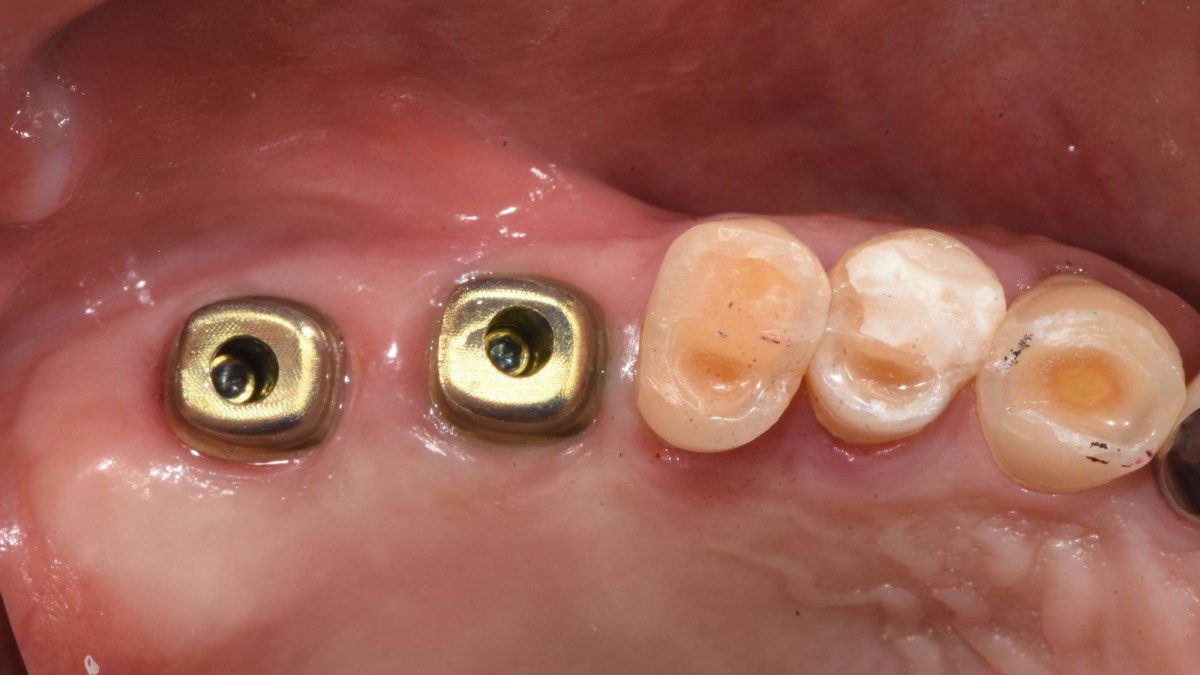

Socket Lift and Implant Placement in the right maxilla.

<GCacg> A 56-year-old male patient complained of pain in the right upper and lower jaws. And he wanted the upper first molar to be pulled out first.